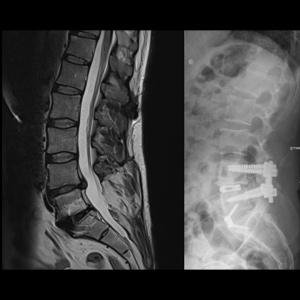

Spinal stenosis (Lumbar) Spinal stenosis (Cervical) Spinal stenosis (Thoracic) Lumbar Disc Herniation Spondylolisthesis Cervical Foraminal Stenosis Vertebroplasty Lumbar Fusion Anterior Cervical Fusion (ACDF) Posterior Cervical Fusion Thoracic Fusion Revision Lumbar Fusion Surgery Facet Joint Cyst Spinal Tumour Minimally Invasive Lumbar Fusion (XLIF) Minimally Invasive Lumbar Fusion (ALIF) Lumbar Fusion (TLIF) Thoraco-lumbar Fusion Lumbar Corpectomy Complex Lumbar Spine Surgery (Spino-pelvic fixation) Complex Cervical Spine Surgery Complex Thoracic Spine Surgery Occipito-cervical Fusion Minimally invasive surgery for thoracic disc herniation Other Related Topics